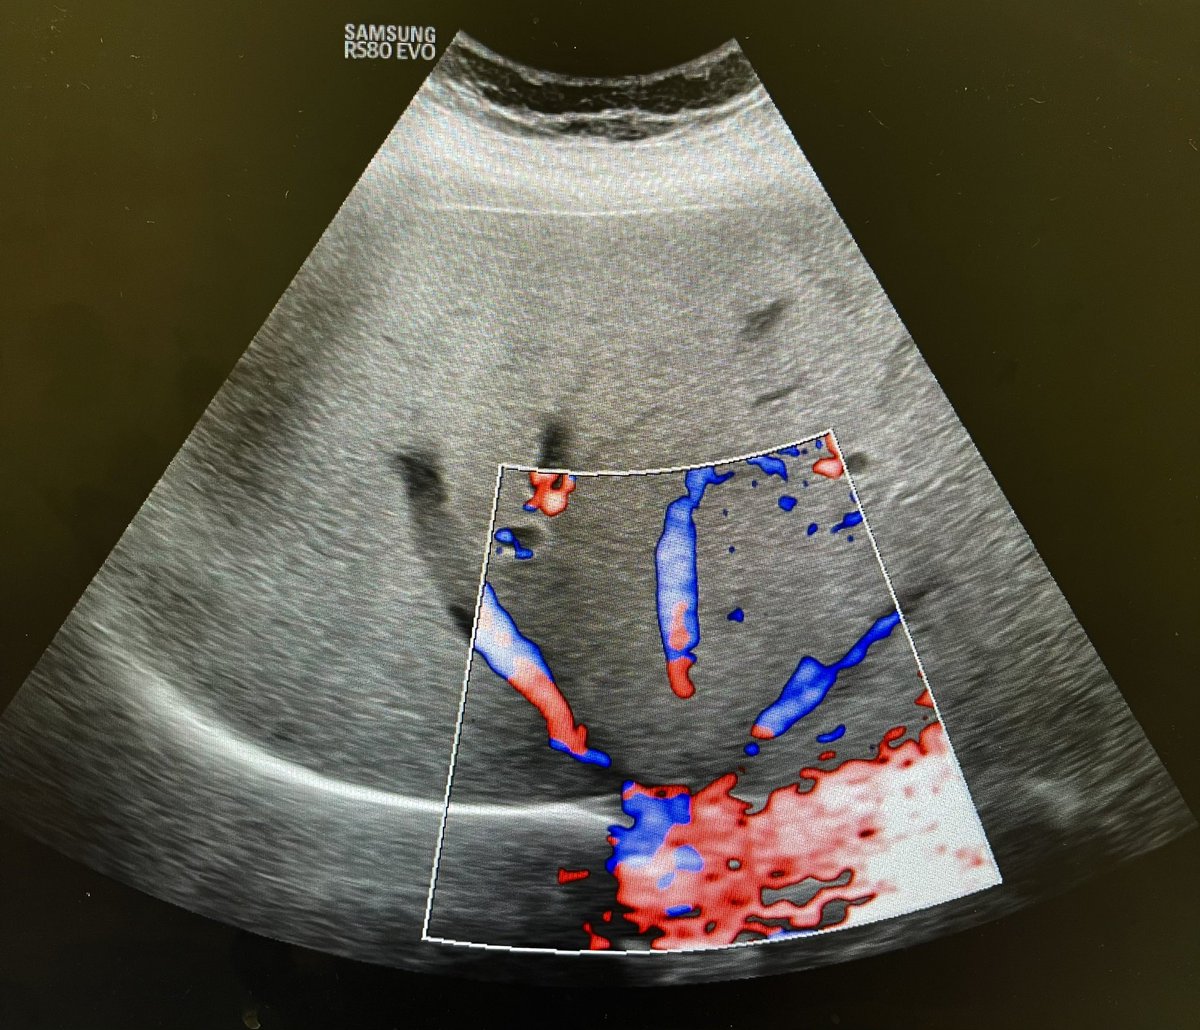

@DeeloOfficial

Deelo

2 days

54F with right flank pain and haematuria. Solid heterogeneous right renal mass with vascularity. ? Renal cell carcinoma. @Rad_Munagi @AjuboDaso